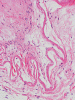

The followings are representative images from autopsy. Panel D to E are taken from the softened area. Panel G and H are taken from the blood vessels of the circle of Willis.